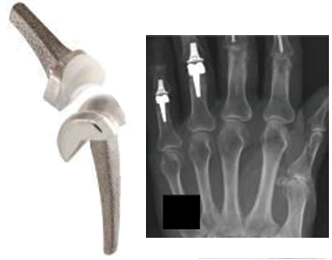

1. **Exactech’s Journey to Bankruptcy**Exactech, once a thriving device manufacturer established by orthopedic surgeons in the 1980s, grew over three decades from a small operation into a significant global entity. The company specialized in surgical implants for joint replacements, including popular lines like Optetrak, Logic, and Truliant for knees, Vantage for ankles, and Novation, Acumatch, and MCS for hips. However, this trajectory of growth took a sharp turn as the company faced an escalating number of lawsuits from patients alleging defective implants.

For knee and ankle replacement devices, Exactech expanded a voluntary recall on February 7, 2022, encompassing all Optetrak, Logic, and Truliant knee replacements, as well as Vantage total ankle replacements. This recall applied regardless of a device’s label or shelf life, because around 80% of these knee and ankle replacement devices manufactured since 2004 were packaged in defective bags. The devices included specific components like various CR and PS Tibial Inserts for Optetrak, Optetrak Logic, and Truliant knees, and the Fixed-Bearing Liner Component for Vantage ankles.

Hip replacement devices were also significantly impacted. In June 2021, Exactech first recalled some GXL Liners for Novation, Acumatch, and MCS hip replacement devices due to premature and excessive wear. Initially, the root cause was unknown. However, by August 2022, Exactech expanded this hip replacement device recall to include all hip devices with polyethylene components packaged in the defective bags, solidifying the packaging defect as the overarching problem. More recently, by March 2024, Exactech voluntarily recalled its Equinoxe Shoulder System implants for the same packaging defects, indicating a wider-reaching problem across multiple product categories.

The lawsuits specifically target Exactech devices manufactured between 2004 and August 2021. To confirm whether your particular implant falls within the scope of these implicated devices, it is essential to meticulously review your medical records or consult directly with your orthopedic surgeon. Should you be uncertain about the brand or specific model of your implant, a qualified product liability lawyer can provide assistance in obtaining and reviewing the necessary medical documentation. The recall encompasses various Exactech product lines, including: Acumatch Hip with Connexion GXL liner; MCS Hip with Connexion GXL liner; Novation Hip with Connexion GXL liner; specific Optetrak Knee components (such as All-polyethylene CR Tibial Components, CR Tibial Inserts, and HI-FLEX PS Tibial Inserts); Optetrak Logic Knee components (including CR Tibial Inserts and PSC Tibial Inserts); Truliant Knee components (like CR Tibial Inserts and CRC Tibial Inserts); and the Vantage Ankle Fixed-Bearing Liner Component.